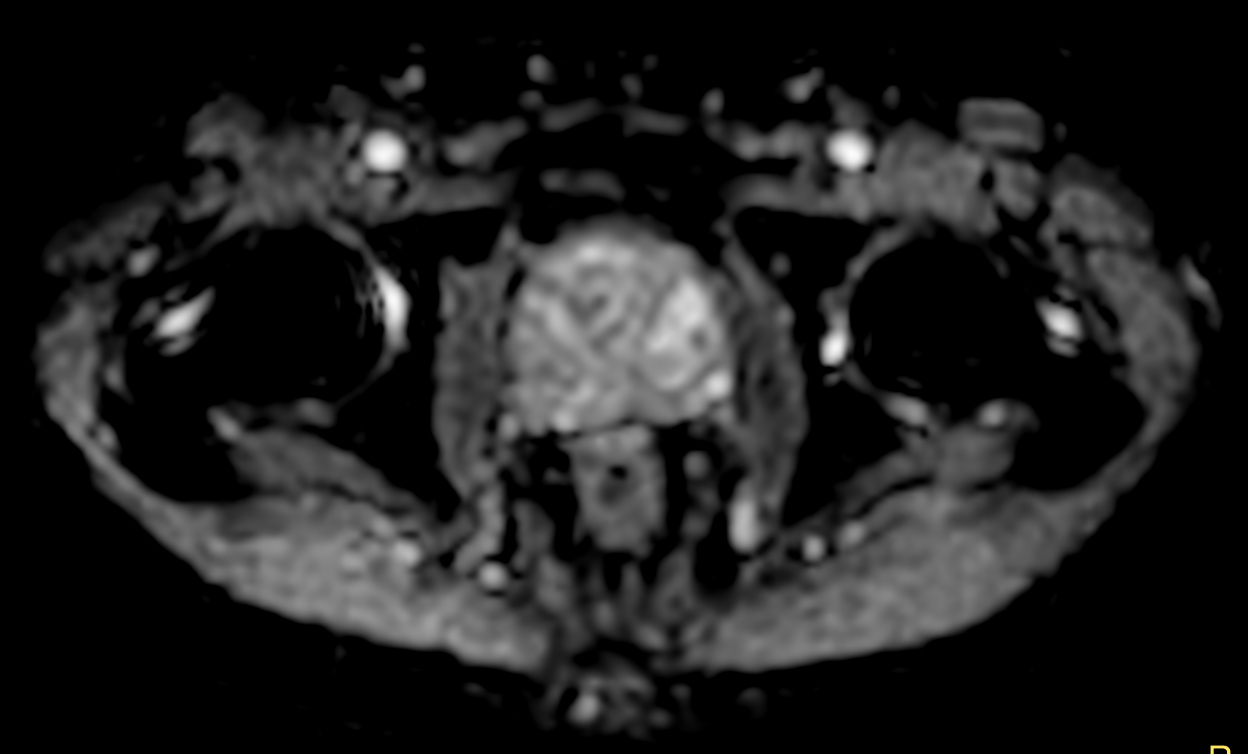

Multi-phase, contrast-enhanced prostate imaging

Patient with a prostate lesion. The ExamCard includes techniques for 3D imaging (PelvisVIEW, eTHRIVE) allowing for multiple image directions in one single scan, efficient fat-free imaging over large field-of-views (mDIXON XD), a multi-phase contrast-enhanced sequence (4D FreeBreathing) to improve imaging confidence and Compressed SENSE to accelerate the entire exam.

DWI b1000

DWI b1000 (ADC)